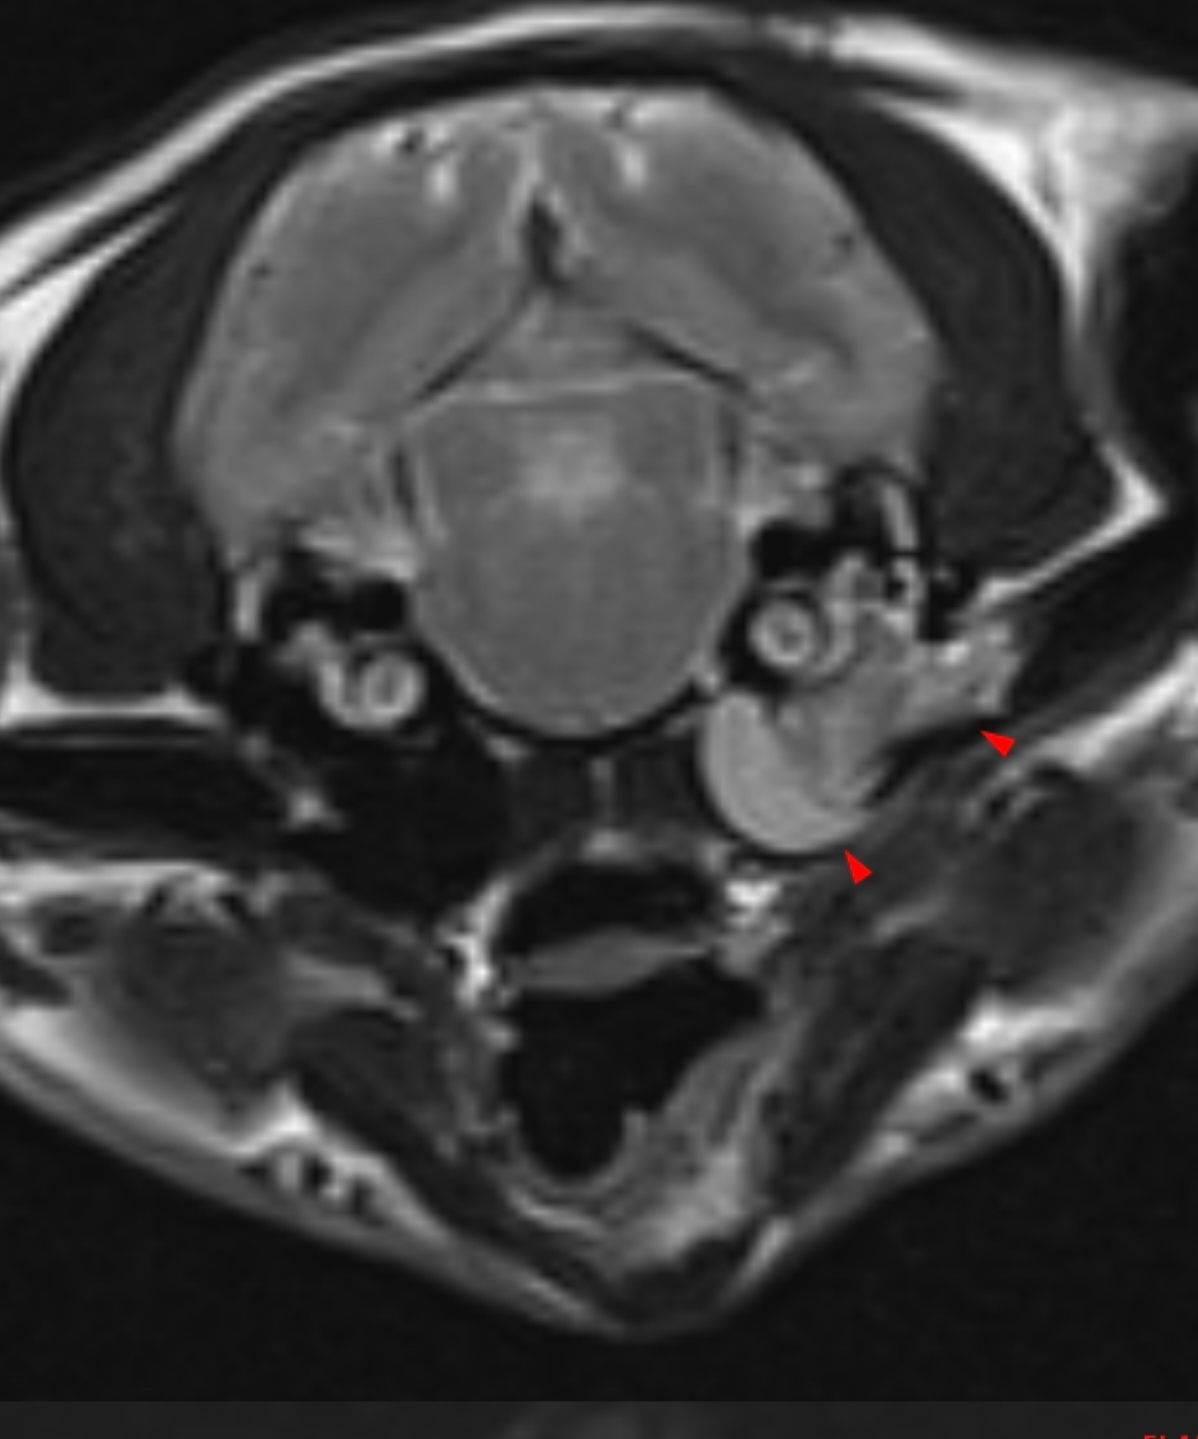

МРТ животным делают только в больших клиниках-госпиталях под наркозом. И такую процедуру я нашла в достаточно дорогой клинике, куда люди приезжали с животными на очень дорогих машинах. Перед МРТ нужно было посетить дерматолога, анастезиолога, сдать анализы и эхо-кг для пожилых животных. Результат показал, что это отит среднего уха. Там же мы сделали операцию по удалению жидкости из уха и ещё раз посетили дерматолога после.

Я потратила на МРТ и анализы для его проведения 25К, сама операция стоила 20К и приём врача в дорогой клинике 7К, мы посещали его дважды. В остальных клиниках где отказались ставить диагноз без МРТ я потратила ещё в среднем по 5К на приёмы офтальмолога, невролога и дерматолога и много анализов и процедур (кровь, бактерии уха, рентген, КТ и тп) ещё около 15к. Также покупала препараты, которые они назначали ещё на 10к (они импортные, редкие и оказались не нужны, т. к. до среднего уха все эти капли не добираются).